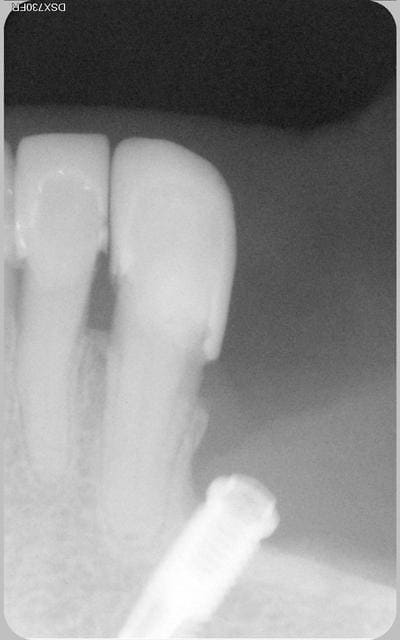

implant posé trop près d'une dent saine

La patiente revenait de l'implantologiste. Je fais une radio de control et je vois ca. La patiente refusait toute prothèse.

Voilà le bébé

La patiente est revenue pour un soin a faire sur 35 qui est bien vivante.

Satisfaite de son coeff masticatoire.

cela fait excactement 9 ans, que l'implant a été posé.

Bien sur et c'est évident que le confrére implanto ne ferait plus ca maintenant.

La nature a bon dos parfois